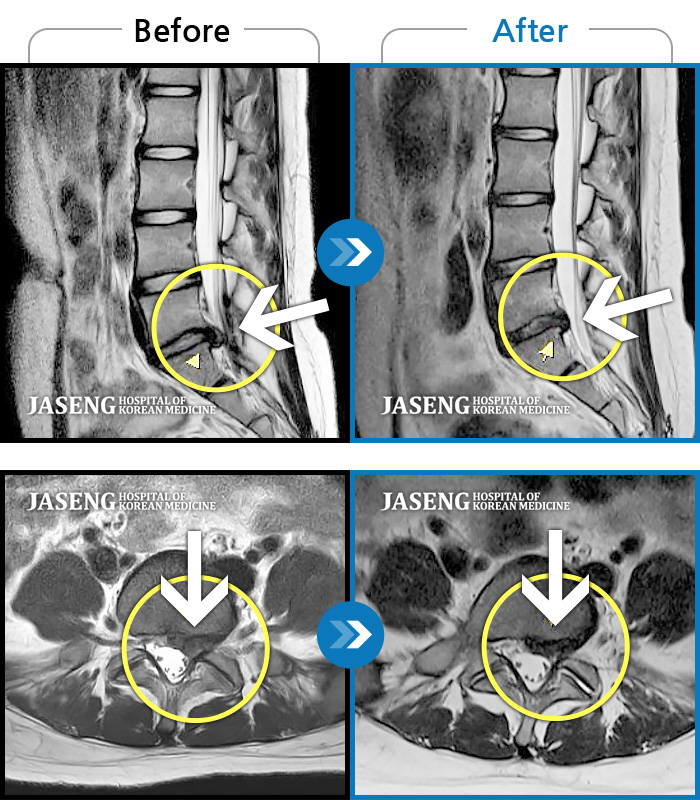

허리디스크

광주 · 김동은 원장

양측 허리부터 양측 골반까지 당기는 통증, 양측 하지 후면으로 이어지는 통증

촬영시기

2022.09.05 ~ 2024.05.06

2024.05.24